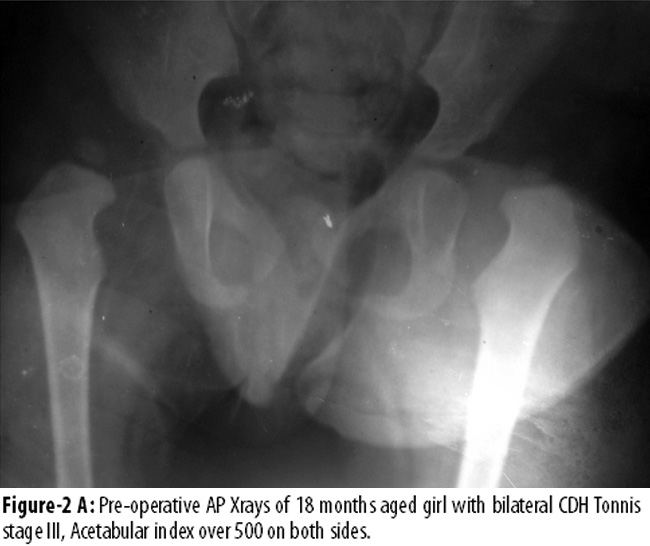

Figure-2AB shows Tonnis level III11 dislocated hips on both sides, with an acetabular index over 50° in an 18 months aged patient.

The successful treatment of CDH depends on concentric initial reduction, its maintenance in a stable position without interference of the blood supply, and an ultimately good remodelling of the hip.7 The results of CDH treatment are directly proportional to the age at the time of initial treatment.9 Treatment of CDH for these late-presenting children of walking age and older is a challenge, as closed or open reduction alone has not proven efficient in achieving successful results. Literature emphasises on additional procedures of femoral and pelvic osteotomy due to soft tissue contractures and structural abnormalities leading to subsequent dysplasia or subluxation. A high rate of very good results are reported with addition of pelvic or femoral osteotomies to open reduction.4,6,11,16,17 One study6 reported 86% clinical and 85% radiological excellent to good results in 23 hips in the age group from 1 year to 4 years treated with open reduction combined with femoral and/or pelvic osteotomies. One study,17 in its small series of 9 hips in 8 patients of similar age group carried out the procedure of simultaneous open reduction and Salter innominate osteotomy, which reported nearly similar 88.88% excellent results. Whereas one study18 reported little less; 77% clinical and 73% radiological good results in 33 hips of 25 older children with similar combined procedure. However, another study4 reported 100% clinical and 92% radiological good to excellent results in age group of 12 to 36 months. It combined Pemberton osteotomy (55%) when the anterolateral coverage of the femoral head was inadequate preoperatively, femoral derotation in 85% and femoral shortening in 4% cases. Similar one-stage combined procedures in same age groups like that study4 were adopted in the current study. However, our results were a little less than others,4,6,17 but nearly similar to some others.12,18,19 We have tried our best in surgery to avoid causing damage to vascularity, labrum and to reduce hip without enforcing tightness or pressure on the femoral head as has been advised in literature.19 Hence, we did not find significant AVN except in one. One study19 based on 1-55 months age group reported that spontaneous development of deep acetabulum can be achieved if the femoral head is maintained in centric reduction without abnormal pressure at any point and by avoiding frequent surgeries to construct the shelf. This, the study said, would allow the nature to play its role in the development of deep acetabulum around the 12th year of age. By this age, Morrison\'s epiphysis appears at the superior and posterior rim of the acetabulum.19 Our study shows the spontaneous mutual growth-stimulating effect of concentric reduction (Figure-1C). Another study12 compared results in various age groups and indicated progressively deteriorating results with increasing age i.e. with addition of every two years at presentation. It reported in a classical review based on long term follow-up, considering age at operation as a significant prognostic factor, 94% acceptable radiological results in younger (<2 years age) children, 80% in age group 2-4 years and 71% acceptable results in children >4 years age and lower incidence of AVN and late growth disturbance in age group <2 years. We always operate bilateral CDH under single anaesthesia to minimise hospitalisation, psychological impact on patient/parents, expenditure and use of medicine (Figure-2). A transfixation K-wire 1.5mm was used to stabilise femoral head in the true acetabulum in almost every hip and a DCP to osteosynthesis proximal femoral osteotomy in children over 30 months of age. Similar to literature20 we did not find any deleterious effect of K-wire as well with DCP in a single case (Figures-1, 2). The other important finding in this study was rapid development of caput femoris epiphysis which had not yet appeared at the time of surgery in the three youngest children and similar was the observation of an earlier study.21 The one-stage combined procedures in older age group reported earlier2,3,7,9,10,22 and others in younger age groups4,7,12,19 revealed clinically better results than radiological. It has been emphasised and concluded by these reports that what looks odd on X-ray i.e. superio-lateral acetabular irregularity (Figure-1C, D and 2C), has no significant bearing on clinical results. Till re-subluxation and AVN development, premature epiphyseal fusion, which leads to short femoral neck and partially uncovered femoral head due to less effective development of acetabulum, as seen in our two cases, have been reported previously.9,12 This acetabular irregularity, as noticed in our previous reports,9,10 has been known to disappear with well-contoured acetabulum on >10 years follow-up.19 Two hips in this study that went to re-subluxations, where one of them was associated with AVN, had no pelvic osteotomy at primary procedure. They required secondary procedure of Salters osteotomy. This further supports the claim of addition of pelvis osteotomy, especially in those hips that have stable hip on Catteral\'s test of stability,12 in position of flexion, abduction and internal rotation. Both the hips achieved good overall rating with recovery from AVN with coxa megna and comparable wide acetabulum on long term follow-up of 5 and 6 years. One case in this study had bilateral dislocation, Tonnis stage IV, and was operated with open reduction, capsuloraphy and Salter\'s osteotomy which developed re-subluxation Tonnis III stage on the left side. Five months after surgery, this patient was re-operated with capsuloraphy, Salter\'s osteotomy and distal derotation osteotomy at age 27 months that did not achieve the desired result. Therefore, she needed another operation with proximal derotation osteotomy and Chiari\'s displacement osteotomy at the age of 5 years. By this time she was diagnosed on re-evaluation to have hyperlaxity syndrome which had not been diagnosed earlier. This girl at seven years follow-up (age 9.5 years) had excellent hip on the right side, but had clinical score fair and radiological rating good on the left side. At 7.5-year follow-up she still walks with hyperlordosis, squats with support, and has developed bilateral pes-plano valgus deformity as well. However, her hips are contained well.